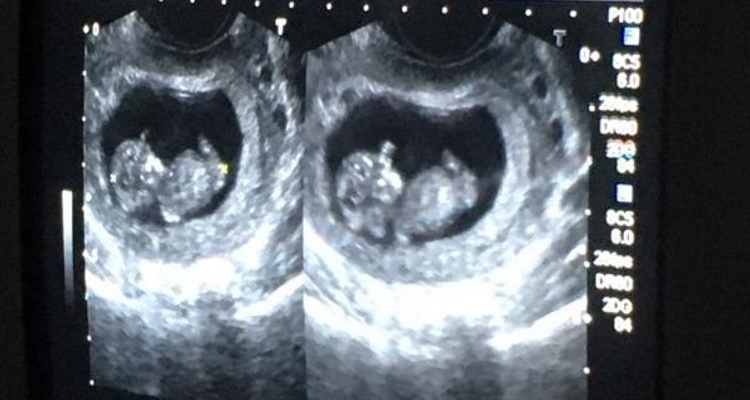

Recently, we shared the story of a woman in Bogotá, Colombia, who had an abortion--only to find out she was still pregnant.

40 Days for Life participants persuaded her to choose life and accompanied her to get a sonogram...

...which the expectant mother graciously shared so that you can see the fruit of your prayers!

Given that an attempt was made on the baby's life, there were fears that the baby might have been harmed during the failed abortion.

Thanks be to God, both mom and child are doing well!